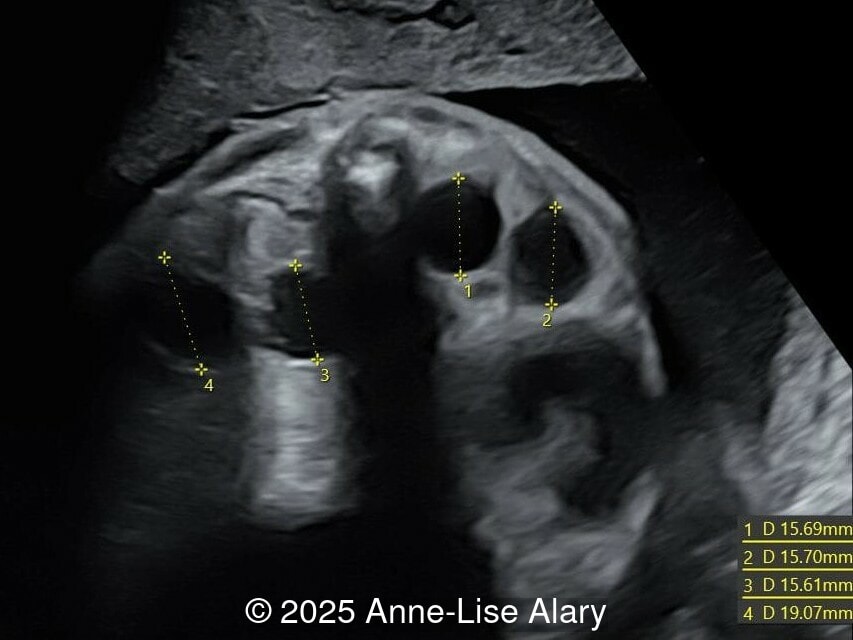

Our prenatal ultrasound revealed a male fetus with megabladder, dilation of both ureter and kidneys, and thinned kidney parenchyma consistent with Lower Urinary Tract Obstruction (LUTO). Additional findings suspected on ultrasound and confirmed on computed tomography included:

- Short long bones (<1st percentile), normal mineralization, and no sign of lethal chondrodysplasia

- Evidence of Potter's sequence due to the lower urinary tract obstruction with small thorax compared to the abdomen, hyperextended neck, and pes varus.

- Dysostosis: Hemivertebrae L3, fused L4-L5, abnormal left foot with short metatarsals and missing phalanges